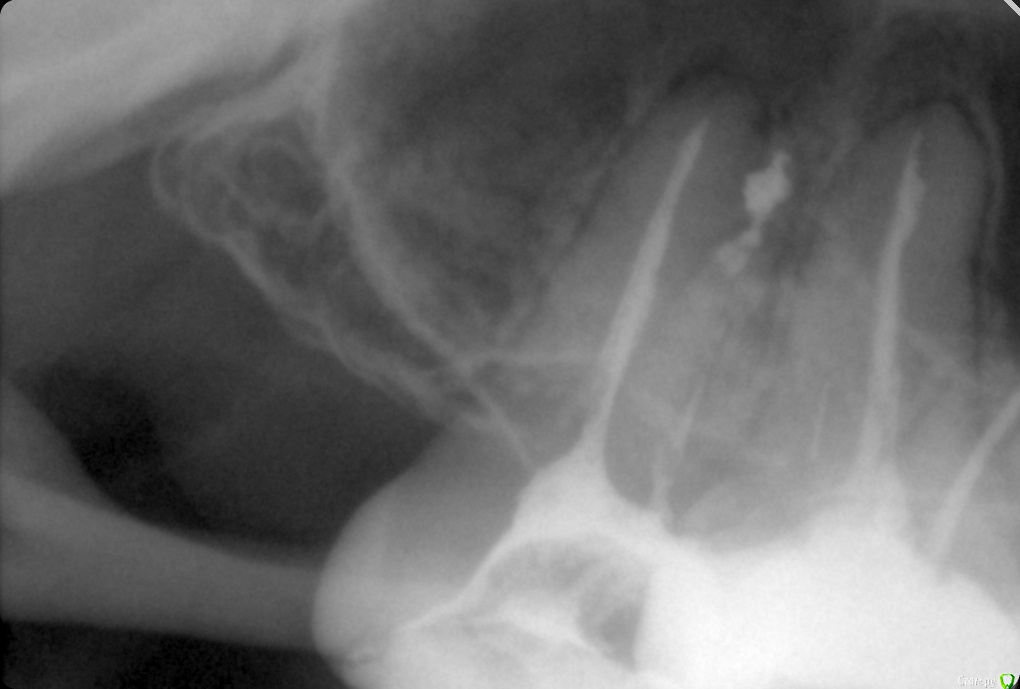

ozbourne87 Опубликовано 5 октября, 2018 Поделиться Опубликовано 5 октября, 2018 Добрый вечер! Подскажите причину боли в зубе(самый последний верхний),второй месяц лечится зуб, кальций закладывали. Пломбировали световой пломбой,потом опять болел зуб, снимали пломбу закладывали что то еще и все равно побаливает. Снимок во вложении-щас в каналах йод с каким то контрастным веществом и временной пломбой Ссылка на комментарий

shishok Опубликовано 6 октября, 2018 Поделиться Опубликовано 6 октября, 2018 А сколько каналов нашли?Мне одной кажется,что медиальный щечный канал пустой? Ссылка на комментарий

ozbourne87 Опубликовано 8 октября, 2018 Автор Поделиться Опубликовано 8 октября, 2018 Два канала нашли Ссылка на комментарий

ozbourne87 Опубликовано 8 октября, 2018 Автор Поделиться Опубликовано 8 октября, 2018 Прилагаю ещё пару снимков Ссылка на комментарий